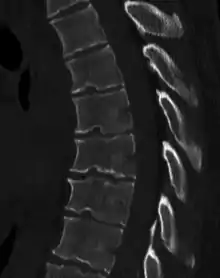

![]() | |

| Scheuermann's disease on lateral Xray of the T spine | |